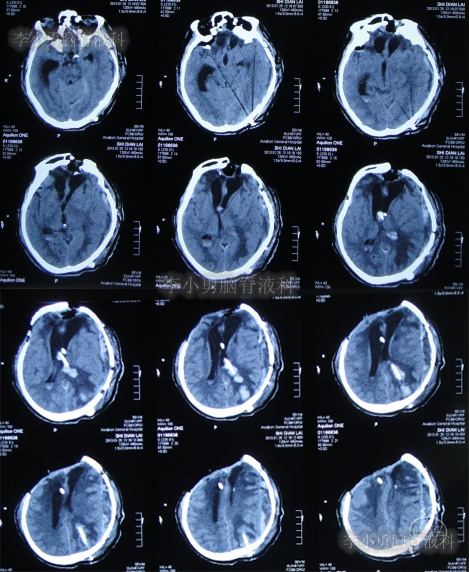

第3家医院出院后26天即2012年9月26日(开颅术后92天),因患者失语、嗜睡、吞咽障碍,第2次住入第3家医院,入院后2天即2012年9月28日,给予伤口及脑内脓肿清创缝合术+脑脊液漏修补术+右大腿取脂肪术,但术后2周即2012年10月12日,复查头颅CT提示脑积水(图-1)。

图-1:2012年10月12日头颅CT

2012年10月16日(第3家医院第2次住院20天),进行了脑室腹腔分流术(图-2)。

图-2:2012年10月16日头颅CT

脑室腹腔分流术后7天即2012年10月23日,患者突发意识丧失、双眼上翻伴头部抖动近20分钟后自行缓解,查头颅CT(图-3)后考虑为“颅内感染”。

图-3:2012年10月23日头颅CT

脑室腹腔分流术后11天即2012年10月27日,进行了脑室腹腔分流管腹腔端外置术(图-4),术中可见清亮脑脊液流出。

图-4:2012年10月27日头颅CT

治疗期间给予腰穿脑脊液检查未见细菌,但白细胞、蛋白偏高,体温仍间断升高,最高38.6度,期间查头颅CT示脑室仍有扩张(图-5)。

图-5:2012年10月30日头颅CT